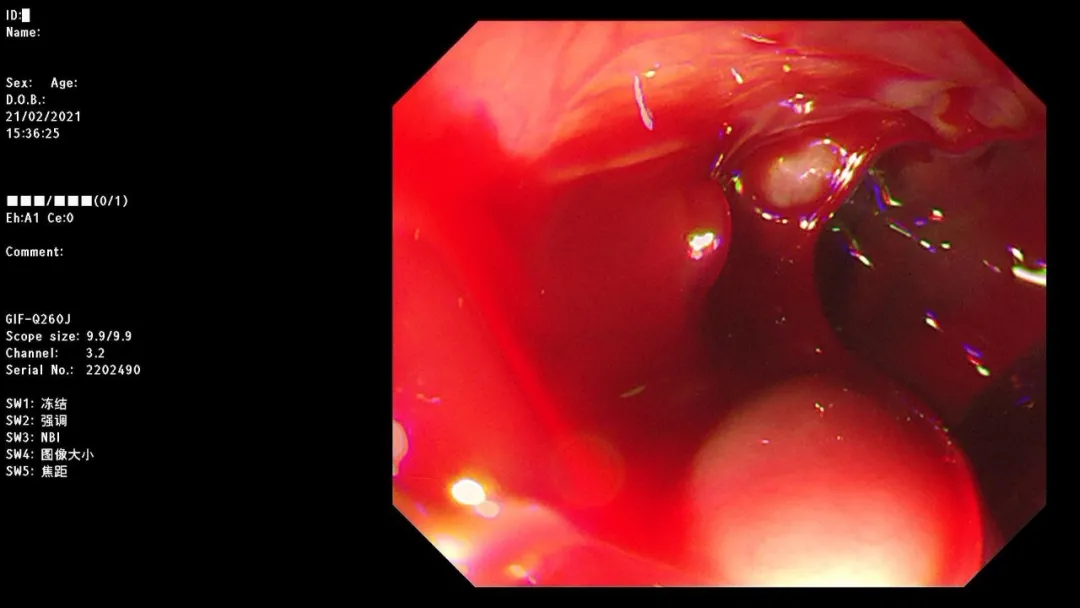

急诊胃镜示:食管距门齿32cm处可见一破口活动性出血,予套扎器套扎治疗,术后无活动性出血,检查诊断:食管静脉曲张破裂出血。